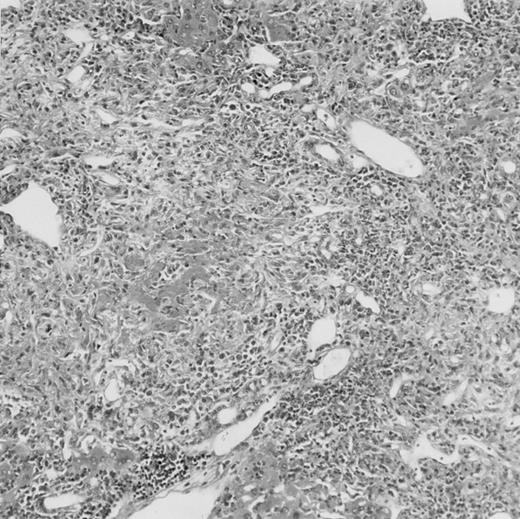

Histologic findings. Organs were collected at different times after BMT and tissue sections were stained with hematoxylin and eosin. Original magnifications for spleen (left) and liver (right) are ×40 and ×100, respectively. (A) B6 mice receiving FVB BM plus EpTK T cells. (B) Control group receiving BM only.

(C) B6 mice receiving FVB BM plus EpΔTK T cells and treated with GCV. (D) B6 mice receiving FVB BM plus EpΔTK T cells, treated with GCV, and developing a late onset GVHD (day 54).

FVB BM-grafted B6 mice: a model of lethal GVHD.We developed a model of GVHD resulting in 100% mortality soon after BMT using FVB mice, a strain not previously used as BM donors in experimental allogeneic BMT. We tested different combinations of recipient irradiation doses, as well as injected BM cell and CD3+ peripheral T-cell numbers. When 10-Gy–irradiated B6 mice were reconstituted with 107 FVB BM cells, we observed prolonged survival, whereas all ungrafted animals died before day 16 (Fig 2). In these conditions, more than 98% of splenocytes were of donor origin (Fig 3A). When 107 CD3+ peripheral T cells from mice of FVB genetic background were added to the FVB BMT, all animals died of GVHD between days 7 and 34 (Fig 2). Similar results were obtained using either PBS-treated mice receiving EpTK or EpΔTK peripheral T cells or GCV-treated mice receiving FVB nontransgenic peripheral T cells. Notably, this observation also indicates that both TK- and ΔTK-expressing T cells in the absence of GCV are fully competent to induce a lethal GVHD. Histopathologic examination of spleen and liver of these animals showed characteristic GVHD lesions such as (1) architecture disruption, necrosis, and congestion in the spleen; (2) hepatic periportal necrosis; (3) mononuclear portal infiltrates; and (4) endothelialitis of portal or centrolobular veinules (Fig 4A). By comparison, B6 mice receiving only FVB BM had a normal histology (Fig 4B).

Protection from GVHD was slightly less efficient in the group receiving EpΔTK CD3+ T cells. The survival rate was 79% at day 60 and 67% at day 120 (Fig 2B). However, two different outcomes must be distinguished. On the one hand, a majority of mice behaved as GCV-treated animals receiving EpTK T cells. They were apparently healthy, presented no skin lesions during a 120-day observation period, and showed complete donor-type hematologic reconstitution. There were no histological signs of GVHD in the spleen or liver (Fig 4C).

On the other hand, 5 of 19 mice exhibited signs suggesting the occurrence of a delayed GVHD (Table 1). Clinically, these animals presented weight loss and/or skin lesions on ears, neck, limbs, or abdomen, but only after day 40. In the absence of any further GCV treatment, 2 mice died 14 and 29 days after the occurrence of these signs (Table 1A) with histological signs of severe GVHD (Fig 4D). These results suggest that, in these mice, the 7-day GCV treatment was sufficient to prevent early, but not delayed GVHD.